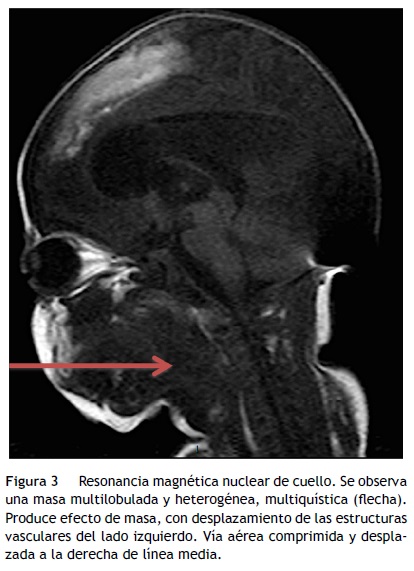

También se realizó una resonancia magnética nuclear (RMN), donde se identificó la presencia de una masa multilobulada y heterogénea, multiquística, de contenido isointenso al músculo en T1, hiperintenso en T2, con componente principal en el hemicuello izquierdo, ocupando los espacios parotídeo y yugular con extensión al parafaríngeo y prevertebral en ese lado, al espacio submandibular, sublingual y parafaríngeo en el lado derecho (fig. 3). Con contacto y desplazamiento de las estructuras vasculares del lado izquierdo en sentido posterior, rodeando parcialmente la carótida interna, producía efecto de masa sobre la vía aérea, la cual se encontraba comprimida y desplazada a la derecha de la línea media.